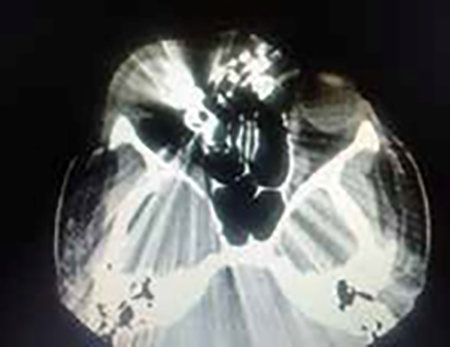

Se solicitaron Rx de cráneo frente perfil, MNP y FNP y tomografía computada, constatándose la presencia de proyectil en ángulo supero-interno de órbita y esquirlas diseminadas. En su pasaje desde su ingreso en la cara anterolateral izquierda y superior de la pirámide nasal el proyectil se fue fragmentando dejando partículas plúmbicas diseminadas. No habiendo signos infecciosos se discontinúa el antibiótico y se mantiene el antiinflamatorio (Figuras 2 y 3).

Figura 2

Figura 3

Figura 6: radiografía de craneo, tomografía computada, radiografía de tórax frente y perfil.